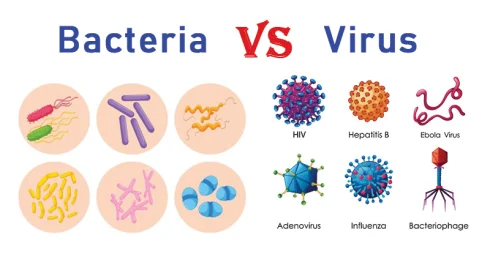

28 تفاوت باکتری و ویروس به همراه مثال

جدول تفاوت باکتری و ویروس شماره ویژگی باکتری ویروس 1. نوع سلول سلول پروکاریوت[بیشتر بخوانید]